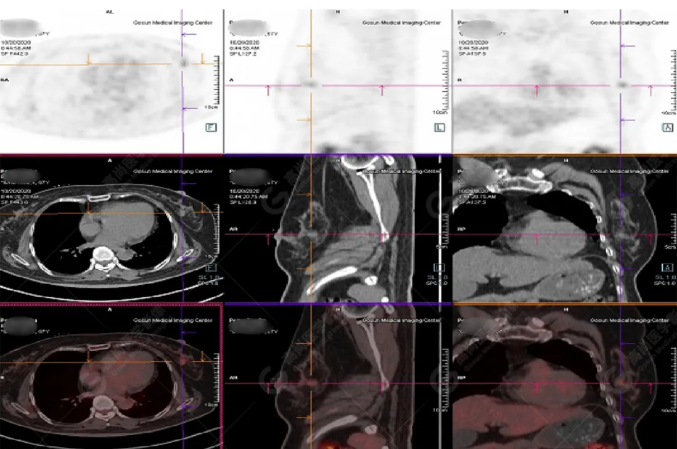

PET/CT影像圖

胸椎溶骨性骨質(zhì)破壞,F(xiàn)DG環(huán)狀代謝增高,SUVmax為4.0。

左側(cè)乳腺一軟組織結(jié)節(jié),F(xiàn)DG代謝增高,SUVmax為2.6。

最終診斷:左側(cè)乳腺癌伴胸椎單發(fā)骨轉(zhuǎn)移。